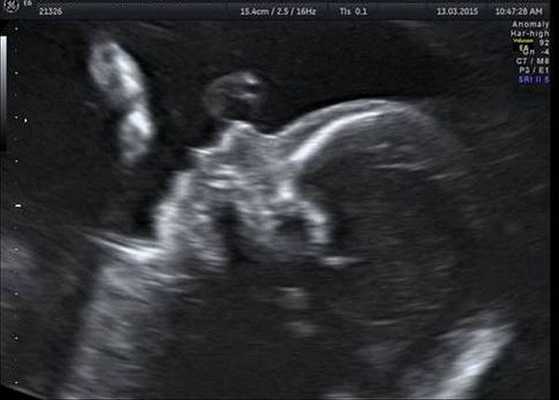

Следовательно, ультразвуковое исследование — использование высокочастотных звуковых волн для создания изображения, подобного тем, которые делаются во время беременности у развивающегося ребенка, — также может проводиться на органах ребенка для выявления любых аномалий. Дополнительные исследования, которые могут потребоваться, включают оценку состояния сердца и проверку слуха.

![Микрогнатия на УЗ-снимке (второй триместр беременности)]()

Генетическое тестирование может быть предложено для подтверждения диагноза, т. е. для исключения генетических состояний, включающих аналогичные лицевые аномалии, связанные с хромосомными и моногенными нарушениями. К таким заболеваниям относятся прогрессирующая гемиатрофия лица, синдром Нагера, челюстно-лицевой дизостоз и др. Однако минимальные диагностические критерии не установлены. Имеются описания единичных случаев диагностики данного синдрома с помощью тестирования до родов.

Индивидуальная профилактика синдрома предполагает проведение медико-генетического консультирования семьи и пренатальной ультразвуковой диагностики беременной женщины в установленные сроки [12] .